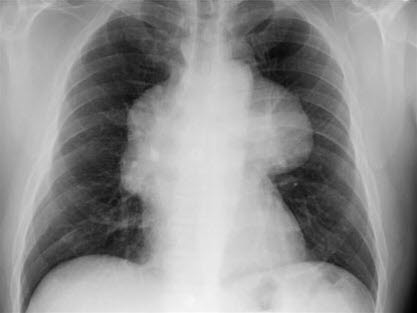

Chorobę można rozpoznać na podstawie zdjęcia rentgenowskiego klatki piersiowej, które często wykazuje poszerzenie śródpiersia i zagęszczenie w zamostkowej, przedniej części śródpiersia.4

Grasiczak - Zmiana ma postać gładkiego zagęszczenia w górnej połowie klatki piersiowej i znajduje się nad górną częścią sylwetki serca na styku serca i dużych naczyń krwionośnych.

- Zagęszczenie jest zwykle rzutowane na jedną z połówek klatki piersiowej.